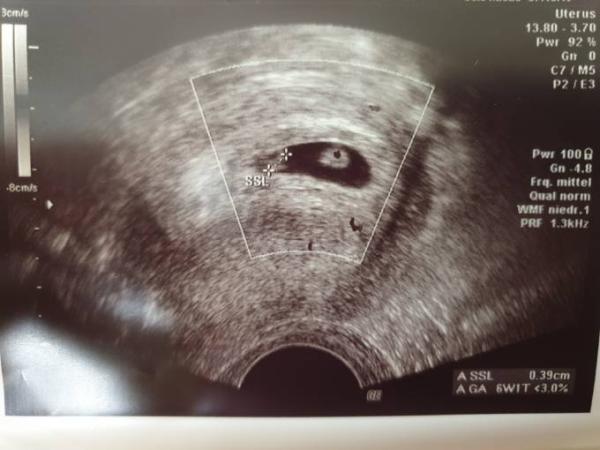

Ihr Lieben, ich darf weiterhin hier bleiben heute bei 6+4 (wurde um ein Tag vordatiert) habe ich erneut einen US gehabt. Ich war ja bereits Montag dort, wo zwei Punkte entdeckt wurden. Eines zeigte da bereits ein Flimmern... heute konnten wir nun zwei schlagende Herzen sehen, es handelt sich um eineiige Zwillinge. Wahnsinn die beiden Kleinen sind 0,39cm und 0,36 cm groß Einzig Kopfzerbrechen bereitet mir nun der nächste Termin am 26.05. Meine FA hat nun 3 Wochen ihren Jahresurlaub. Normalerweise sollte man ja am Anfang auch schauen, ob die beiden direkt zusammen liegen oder jeder seine eigene Amnionhöhle hat, also ob es quasi Mono-Mono oder Mono-Di-Zwillinge sind (las da was von 9.SSW an...). Habe Angst, dass ich da irgendwo einen Zeitpunkt verpasse, weil man das wohl nur in einem gewissen Zeitraum sehen kann. Kennt sich hier jemand aus?